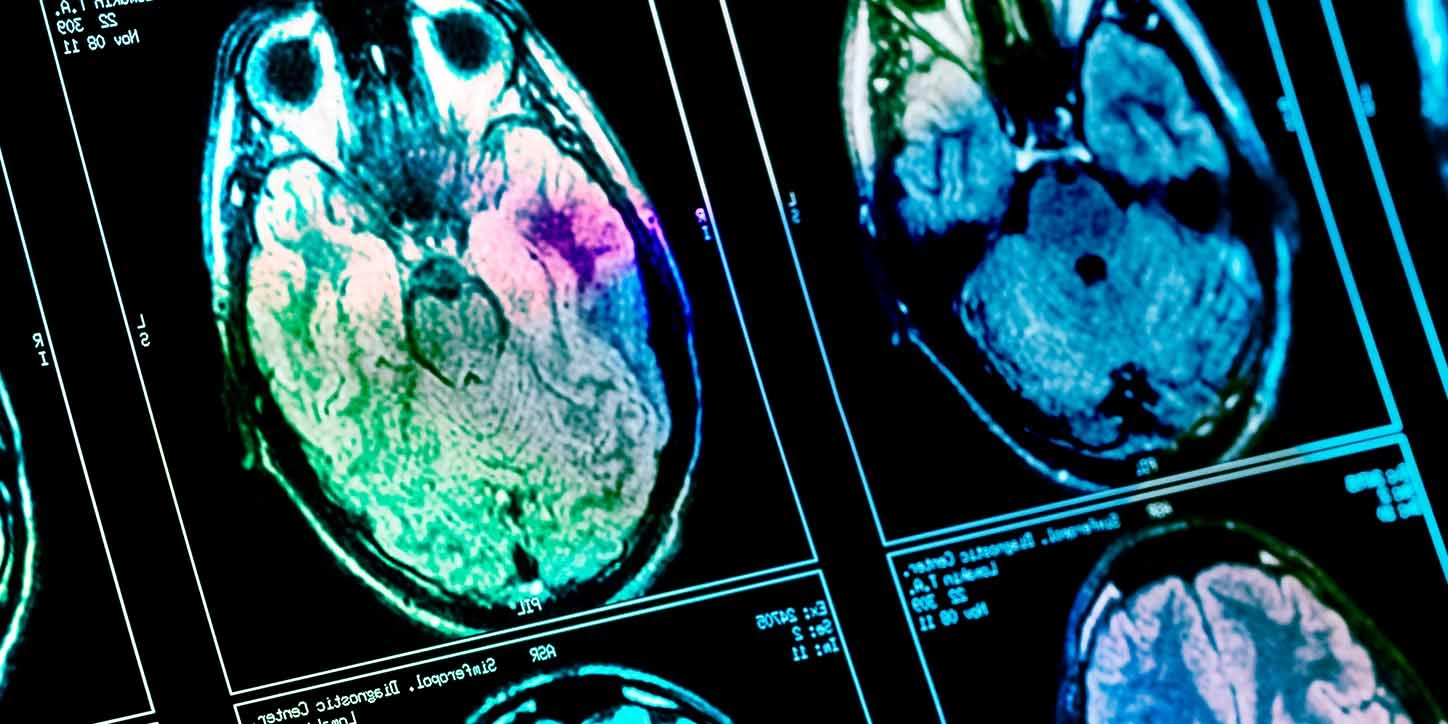

Categoria: Parkinsonismo

O que são os parkinsonismos atípicos? Quando falamos em Doença de Parkinson, logo pensamos em tremor, rigidez e […]

O que é a Degeneração Corticobasal? A Degeneração Corticobasal (DCB) é uma doença neurodegenerativa rara que faz parte […]

O que é a MSA? A Atrofia de Múltiplos Sistemas (MSA) é uma doença neurológica rara, degenerativa e […]

O que é a PSP? A Paralisia Supranuclear Progressiva (PSP) é uma doença neurodegenerativa rara, mas considerada o […]